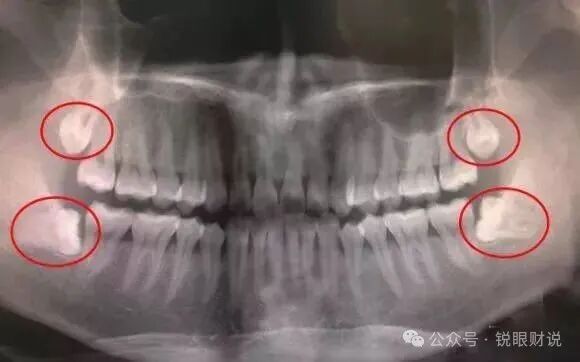

智齿,这个位于口腔最后方的第三磨牙,经常被人们视为多余的牙齿。

然而,智齿在口腔中扮演着重要的角色,具有一定的咀嚼功能和支撑作用。

智齿的存在可以帮助我们更好地咀嚼食物,尤其是较硬的食物。同时,它们还能够支撑周围的牙齿和牙槽骨,保持口腔的稳定性。

如果智齿被拔掉,可能会导致邻牙松动、牙槽骨吸收等问题,影响口腔的健康和美观。

当然,智齿的生长过程可能会引发一些问题,如智齿冠周炎等。

这主要是由于现代人的颌骨变小,而智齿的大小并没有相应减小,导致智齿无法完全萌出或位置不正。

在这种情况下,医生可能会建议拔掉智齿以避免潜在的问题。

然而,在做出决定之前,我们应该充分了解所有可能的风险和后果。

如果智齿的生长状况良好,没有出现任何问题,那么保留智齿并对其进行适当的保养和清洁是更加明智的选择。